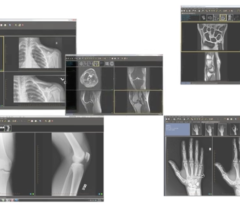

Radiology departments have many different needs and face a wide variety of challenges that can impact their departments ...

Bayer Radiology’s Barbara Ruhland and Thom Kinst discuss how radiology departments can address the many different ...